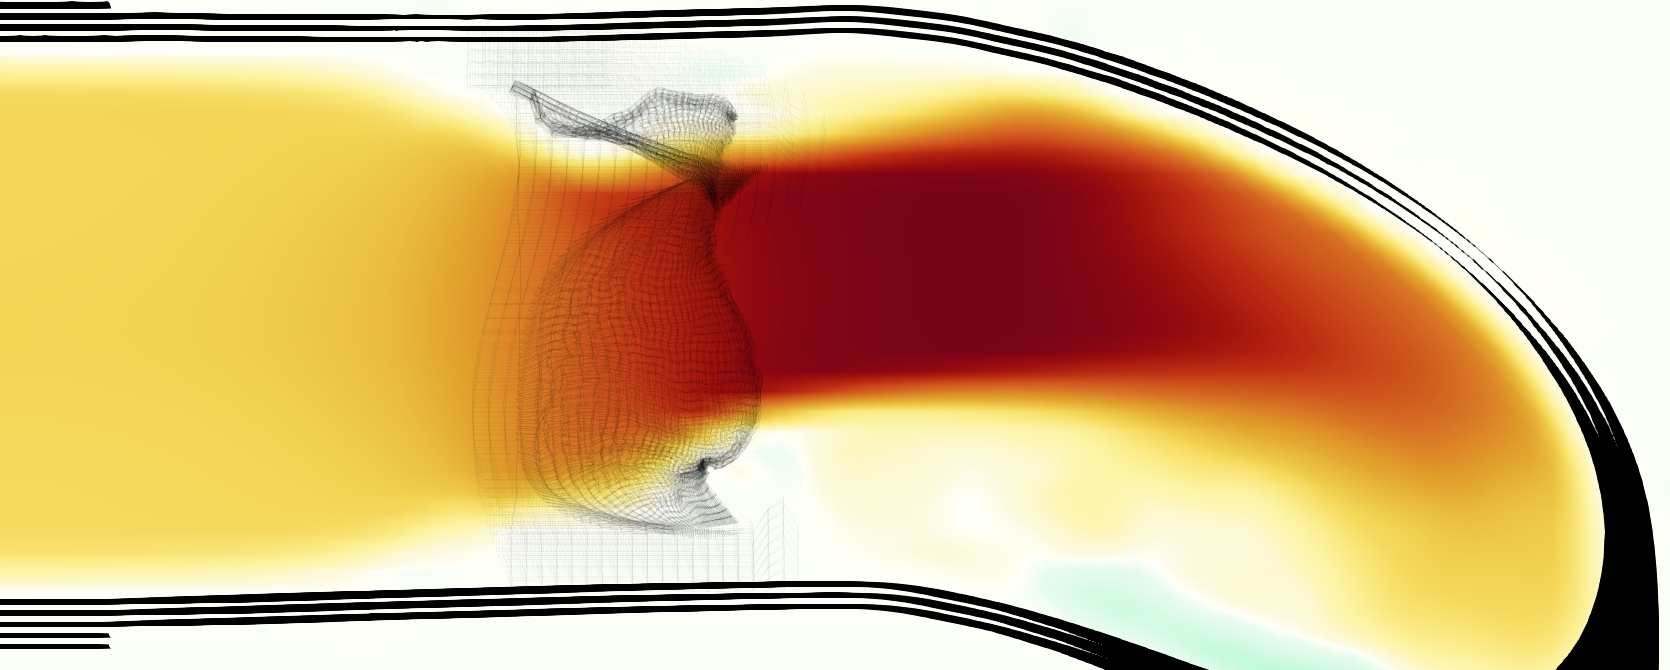

The emergent hemodynamics showed excellent qualitative agreement with experiments. Slice views of the axial component of fluid velocity ( component) in the sagittal plane that cuts through the center of the vessel, parallel to the flow direction, are shown in Figure 5. The flow in both the simulation and the experiment began to accelerate at the same time, with a jet forming through the open valve leaflets. The velocity, angle, and shape of the jet agreed well between the two cases during systole. The simulation captured the slight upward angle of the jet, which was not fully centered in the vessel. It also matched the location where the jet impacts the wall and the slower speed of the jet as it turns with the MPA downstream. As the flow decelerated, the fluid along the interior curve of the vessel reversed first while forward flow persisted where the jet was strongest, as seen in both the simulation and experimental results.

In both the experiment and the simulation, a separation region of reverse flow developed along the interior curve of the vessel under the core jet through the valve. The reverse flow began to develop at the same time in the cardiac cycle and grows throughout systole. The simulation lacked reversed flow in the entire region where reversed flow was present in the experiment, but this region developed some flow separation and had much slower flow than elsewhere in the vessel. Thus, the simulation captured that this is a distinct region from the core jet through the valve opening. There was a smaller amount of slower and slightly reversed flow along the outer curve of the vessel, close to the valve annulus and scaffold support. This region was well-matched between the experiment and the simulation.